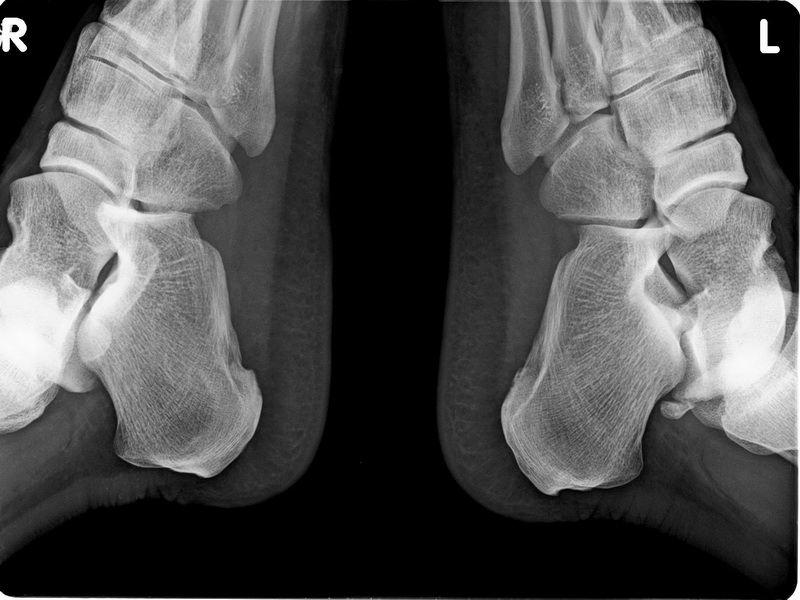

标题: X6080:双跟骨轴侧位,有双侧跟骨骨刺形成吗?好像是跟骨结 [打印本页]

标题: X6080:双跟骨轴侧位,有双侧跟骨骨刺形成吗?好像是跟骨结

双跟骨轴侧位,有双侧跟骨骨刺形成吗?好像是跟骨结节呀?

双侧跟骨下结节处未见明确骨刺形成。

双侧跟骨下结节处未见明确骨刺形成--------------

未见明显骨刺形成,但是侧位不侧,像斜位

比较毛糙,还是有骨质增生

我认为在私营医院,最多弄个轻度骨质增生诊断,要说双侧跟骨骨刺形成,就太过度了。如是在公立医院我就当正常好了,等以后真得有骨刺了再报也不迟。

双跟骨下结节未见明显骨刺形成。